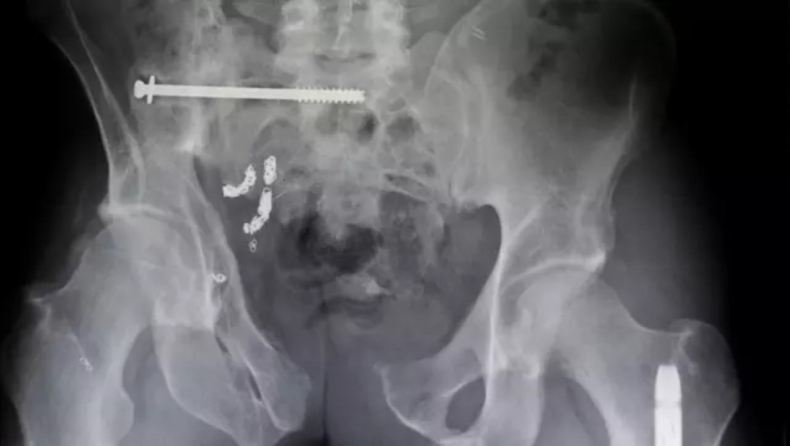

Χιλιάδες άνθρωποι νοσηλεύτηκαν το 2025 για ξένα αντικείμενα στα οπίσθια, με τις αμερικανικές αρχές να δίνουν στη δημοσιότητα μια λίστα που προκαλεί ιδιαίτερη αμηχανία...